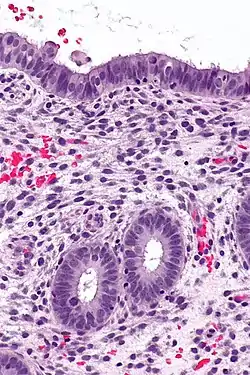

|  Endometrium in the proliferative phase | |

The endometrium consists of a single layer of columnar epithelium plus the stroma on which it rests. The stroma is a layer of connective tissue that varies in thickness according to hormonal influences. In the uterus, simple tubular glands reach from the endometrial surface through to the base of the stroma, which also carries a rich blood supply provided by the spiral arteries. In a woman of reproductive age, two layers of endometrium can be distinguished. These two layers occur only in the endometrium lining the cavity of the uterus, and not in the lining of the Fallopian tubes.[3][4]